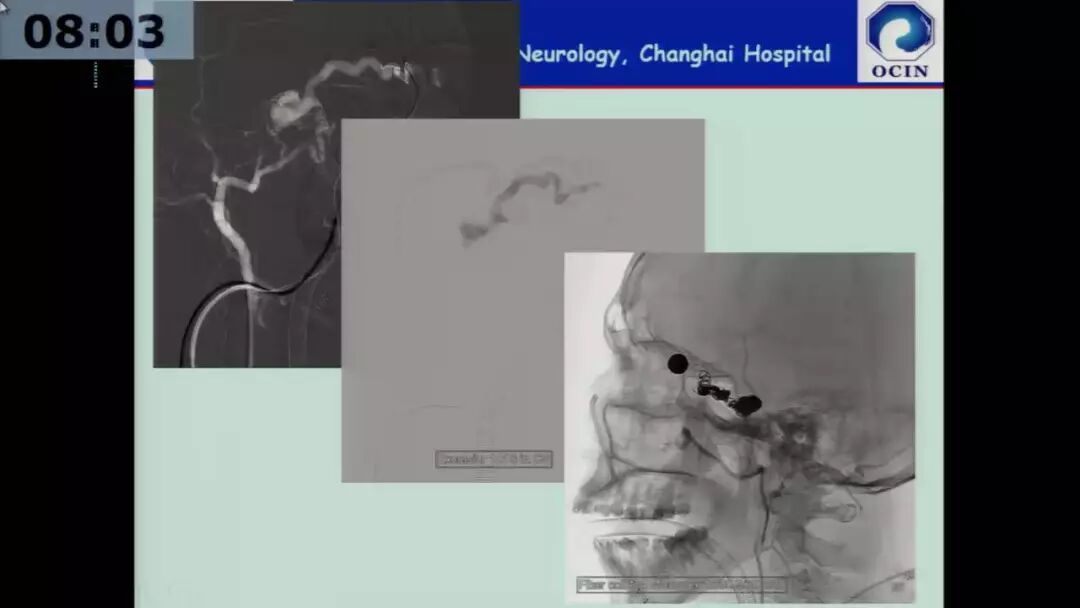

今天为大家分享的是由海军军医大学附属长海医院许奕教授在四川省医学会第十二次介入医学学术暨西南神经介入高峰会议上带来的“海绵窦区脑膜动静脉瘘的介入治疗”精彩讲课视频和PPT,欢迎观看!(内容未经讲者审核,不当之处请与我们联系)

许奕教授:海绵窦区脑膜动静脉瘘的介入治疗